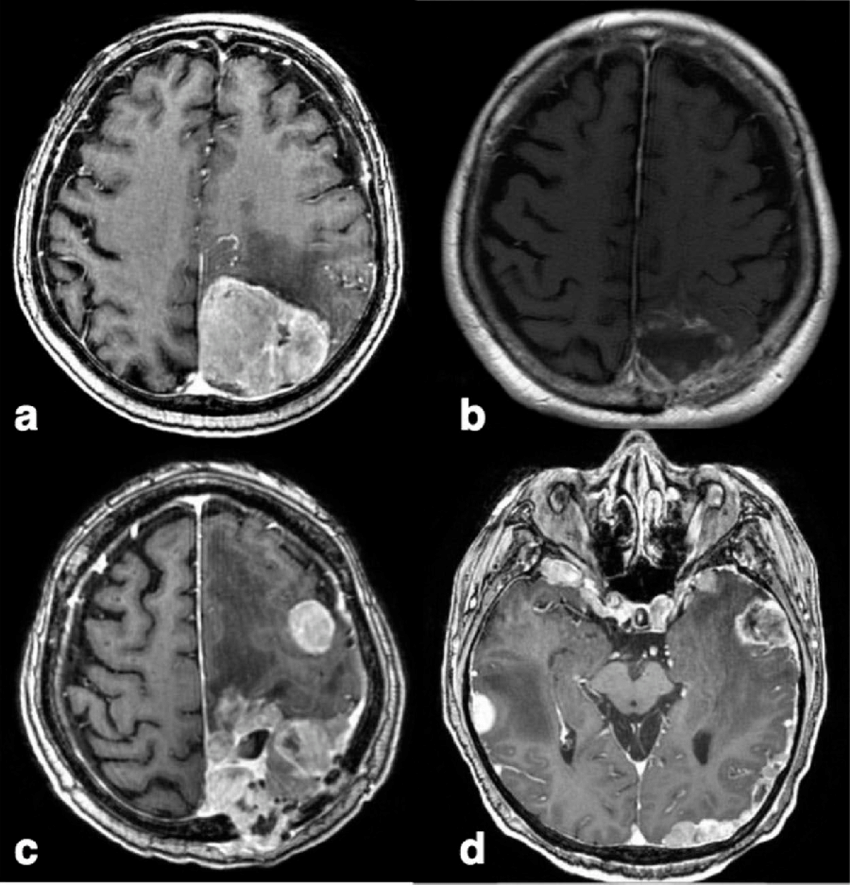

診断

MRI(磁気共鳴画像) MRIは髄膜腫の診断において最も重要な手法の一つです。以下のような特徴を持ちます:

- T1強調画像: 髄膜腫は一般的に等信号を示し、造影剤(ガドリニウム)を使用すると強く造影されます。これは腫瘍の血管が豊富であるためです。

- T2強調画像: 髄膜腫は等信号または高信号を示すことが多く、腫瘍内の構造や浮腫の有無を確認するのに役立ちます。

- フレア画像(FLAIR): 水分を強調することで腫瘍の輪郭をより明確にすることができます。